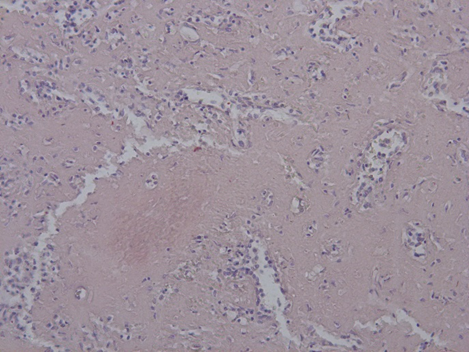

Гистологическое исследование. Сердце – кардиомиоциты гипертрофированы, диффузный кардиосклероз. При окраске на амилоид в строме и стенке сосудов отложение амилоидных масс (рис. 1). Селезенка – красная пульпа полностью замещена однородными массами, дающими положительную окраску на амилоид (рис. 2).

Рис. 5. Пролиферация клеток костного мозга. Окраска гематоксилин-эозин, ×200